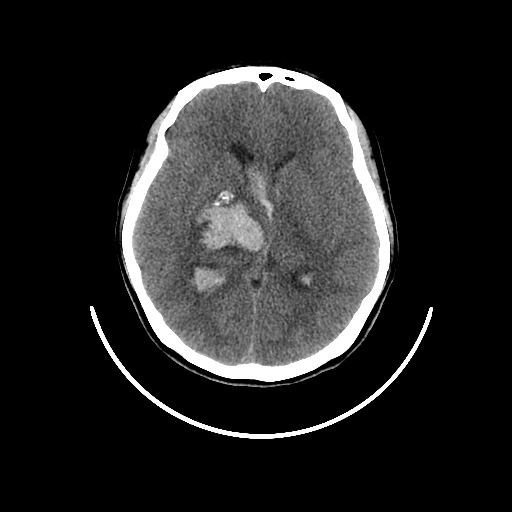

내가 정식으로 진단받은 병명은 ‘동정맥기형 파열에 의한 뇌내출혈’이다. 나는 뇌혈관이 터져버리는 출혈성 뇌출혈로 진단받았고, 출혈 부위는 대뇌, 그 중에서도 기저핵과 시상일부로 여러 부위에 걸친 대형의 기형혈관이 터지면서 뇌손상을 입었다. 고혈압이나 당뇨 등 기저질환을 앓고 있지도 않았는데 갑작스런 뇌출혈로 고생하는 젊은 뇌졸중 환자들은 대부분 이 동정맥기형 때문인 것 같았다.

동맥에서 모세혈관을 거쳐 정맥으로 흐르는 것이 정상인 혈류가 모세혈관을 거치지 않고 동맥에서 정맥으로 직접 흘러서 생기는 비정상적인 혈관의 집합체를 말한다. 중간에 이상 혈관 덩어리인 혈관괴(血管塊)가 생긴다. 주로 대뇌의 표면부에서 안쪽으로 걸쳐서 생기지만 깊은 부위에서 생길 수도 있다. 혈관괴는 성장함에 따라서 조금씩 커지며, 동정맥기형 내의 혈류 속도도 점점 빨라진다. 남자가 여자보다 약간 더 많이 발생하며, 유병률은 0.14%가 조금 넘는 것으로 알려져 있다. 발병연령은 약 33세 전후로 이 가운데 64%가 40세 이전에 진단을 받는 것으로 알려져 있다. 다음의 4가지 신경학적인 증세가 나타난다. ① 뇌출혈 : 동정맥기형이 파열되어 나타나는 증세로 30세 이전에 일어나는 뇌출혈의 가장 많은 원인을 차지한다. 갑작스러운 구토, 두통, 반신마비, 의식변화 등이 생긴다. 출혈이 일어날 때마다 신경학적인 결손을 나타내는 경우가 30∼50%, 사망률이 10%인 것으로 알려져 있다. ② 전간 : 뇌동정맥기형이 주위의 조직을 자극하여 일어난다. 나이가 어릴수록 전간이 일어나는 경우가 많다. 많이 발생하는 연령은 약 25세로 알려져 있고, 뇌동정맥기형의 크기가 클수록 전간에 의한 증세가 많이 나타난다. ③ 편두통 : 뇌동정맥기형 자체가 주위 신경조직을 눌러서 생긴다. 한쪽에 심한 두통이 나타나는데 일반적인 편두통과의 구별이 어렵기 때문에 정밀검사가 필요하다. ④ 뇌빈혈 : 기형이 있는 주위의 뇌에 충분한 혈액 공급이 안되어 생기는 것으로 반신마비, 언어장애, 감각이상 등의 증세가 나타난다. 치료방법은 다음과 같다. ① 수술 : 개두술로 뇌동정맥기형을 제거하는 것이다. ② 방사선수술 : 기형핵이 약 3㎝ 이하인 뇌동정맥기형인 경우에 시행하는 것으로 기형핵에만 방사선을 국소적으로 조사하는 방법이다. ③ 혈관내색전술 : 혈관 안으로 도자를 넣어서 색전물질을 기형핵에 주입하여 기형혈관을 막는 방법이다. [네이버 지식백과] 뇌동정맥기형 [cerebral arteriovenous malformation, 腦動靜脈畸形] (두산백과 두피디아, 두산백과)

뇌CT,MRI,혈관MRI(왼쪽위부터시계방향으로)-아래사진 좌측윗부분의 혈관뭉치가 기형혈관)